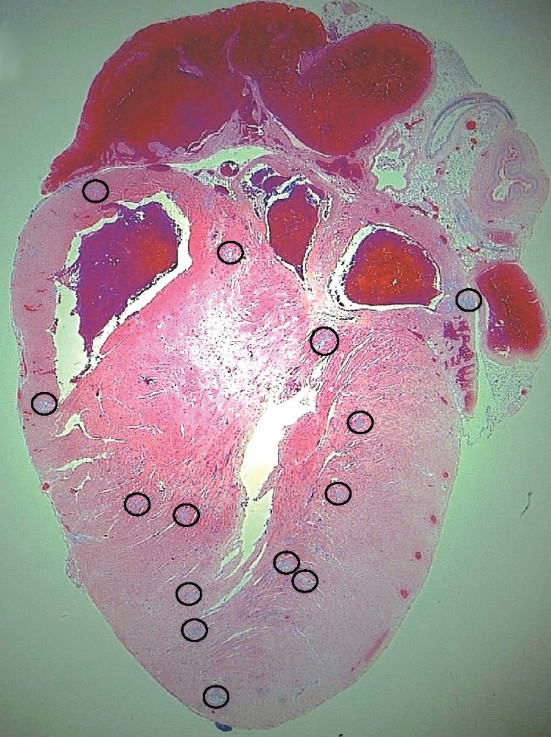

I topi con malattia pneumococcica invasiva grave hanno mostrato elevati livelli di troponina, un marker di danno cardiaco, nel loro sangue ed elettrocardiogrammi anormali. Quando i ricercatori hanno esaminato i cuori dei topi, hanno scoperto siti con microscopiche lesione (microlesioni) nel muscolo cardiaco. S. pneumoniae sono stati trovati all’interno di queste microlesioni, indicando che i batteri sono stati in grado di invadere e moltiplicarsi all’interno del cuore. Osservando più in dettaglio, i ricercatori hanno scoperto delle cellule del muscolo cardiaco morte, nel tessuto circostante le microlesioni. A livello molecolare, i ricercatori hanno scoperto che la tossina pneumolysin, prodotta dal batterio S. pneumoniae, era presente all’interno delle microlesioni e responsabile della morte delle cellule del muscolo cardiaco.

Nei tessuti di tre macachi rhesus che erano morti di polmonite pneumococcica, i ricercatori hanno scoperto microlesioni cardiache che erano simili nelle dimensioni e nell’aspetto a quelle osservate nei topi, ma senza la presenza di S.pneumoniae batteri. La situazione era simile nei campioni cardiaci di pazienti umani che erano morti di malattia pneumococcica invasiva. Due dei campioni (ne sono stati esaminati nove) hanno mostrato microlesioni, ma le lesioni non contenevano i batteri. Poichè i macachi e i pazienti umani erano stati trattati con antibiotici, i ricercatori hanno verificato se ” i batteri avevano causato le lesioni ” e successivamente erano stati uccisi dal trattamento. Per verificare ciò, essi hanno sottoposto a trattamento antibiotico, topi che erano stati infettati da S. pneumoniae.  I cuori di questi topi sembravano simili a quelli dei macachi e campioni umani, con la chiara presenza di microlesioni, ma privi di batteri.